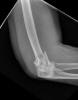

Fractura de olécranon con osteosíntesis.